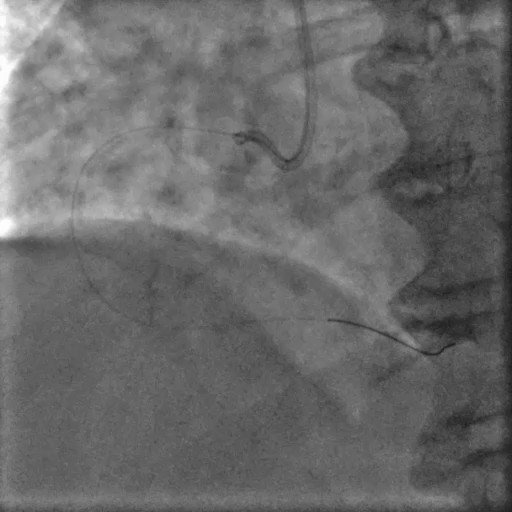

Mechanical SAVR with acute decompensation, emergent cath Watch on X

Mechanical SAVR Cardiogenic shock New LBBB

Acute decompensation in patient with mechanical aortic prosthesis

Patient with prior SAVR (mechanical prosthesis, 20-year history) presenting with acute dyspnea, cardiogenic shock (BP 80/40) and new LBBB on ECG. Referred for emergent catheterization. Vignette highlights the diagnostic challenge of suspected mechanical valve dysfunction versus acute coronary syndrome in a hemodynamically unstable patient.

History: SAVR 20y

Hemodynamics: Shock 80/40

ECG: New LBBB

Setting: Emergent cath